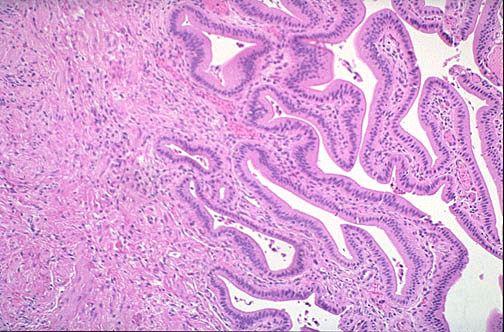

Stomach

1Gastric pits

2Gastric glands

3Mucosal lining

+1 more points